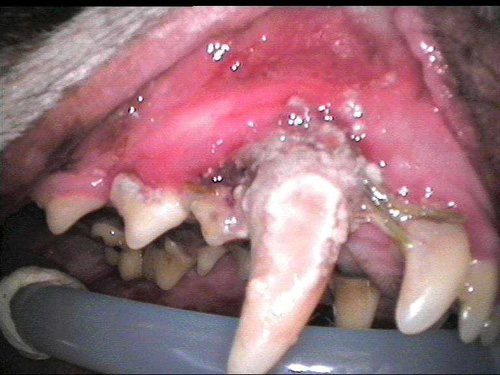

Dent tartar 1-5

CL1-3